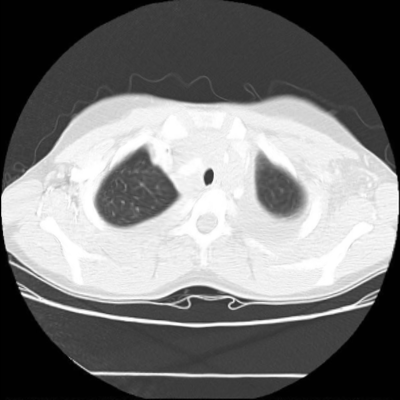

We then test our method on slices of chest CT images obtained from the Open Access Biomedical Image Search Engine [2]. Fig. 10(a) and 10(b) show the source image and target image respectively, and the intensity difference is shown in Fig. 10(c). The registration result obtained by our proposed method is shown in Fig. 10(d) (see also the result with the deformed underlying grid in Fig. 10(e)). From the final intensity difference plot in Fig. 10(f), it is easily to see that our method matches not only the two large components but also the small dot at the center very well. On the contrary, DDemons [47] produces a suboptimal registration result with a significantly larger mismatch of the small component at the center (see Fig. 10(g) and Fig. 10(h)).